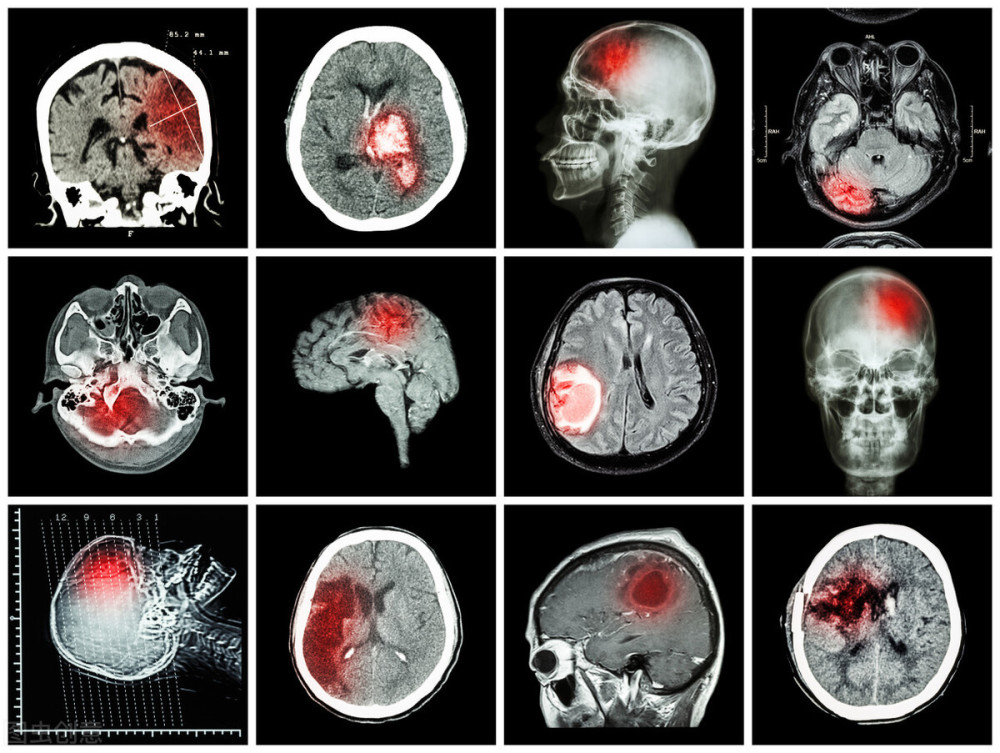

其实脑梗就是因为脑部血管发生堵塞 , 大脑的神经组织缺血缺氧而出现软化坏死 , 威胁了患者的生命健康 。 一旦脑梗发作 , 很有可能会危及生命 , 就算救治得及时 , 一些患者也会因为脑梗的面积和程度较大 , 留下偏瘫 , 半身不遂的后遗症 。

文章插图